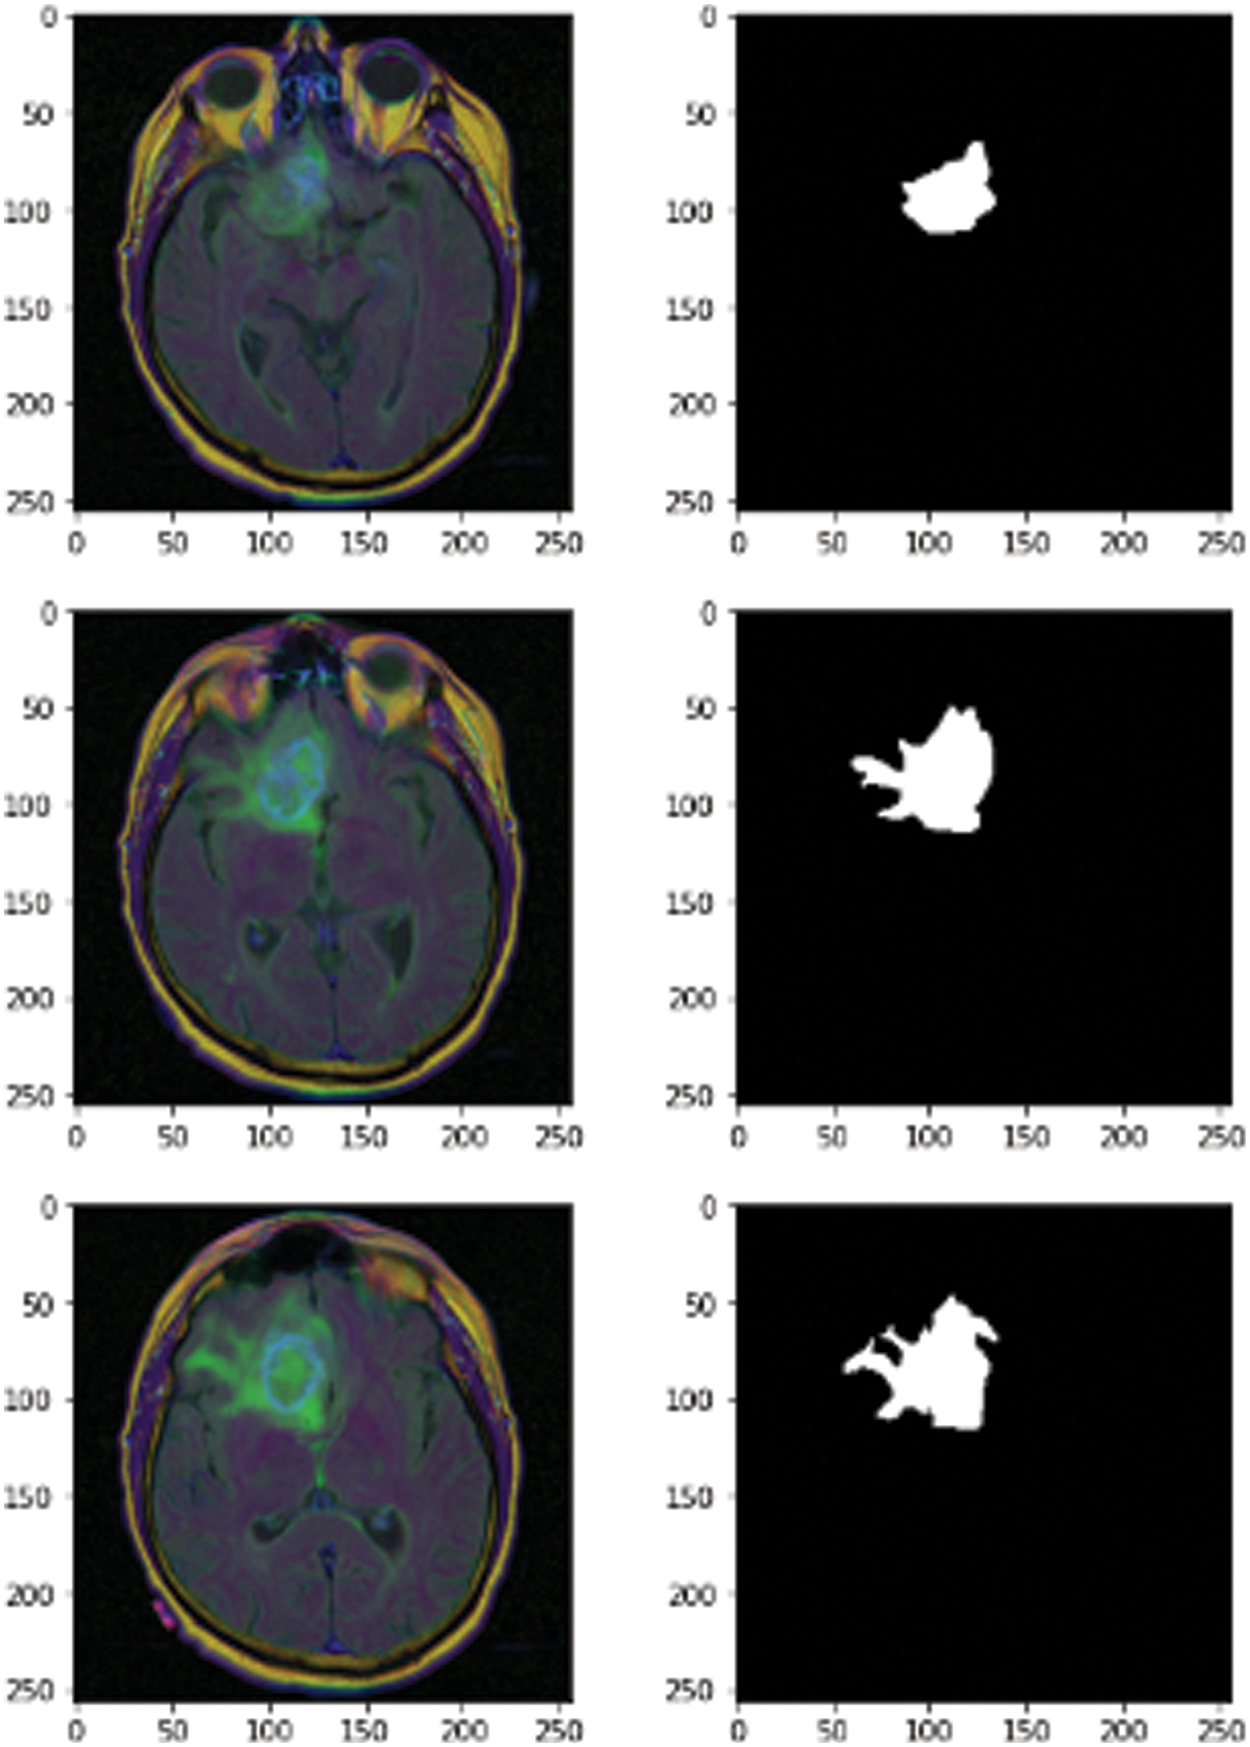

The novel methodology used a dataset from Kaggle called the Low Grad Glioma (LGG) Segmentation Dataset, which contains brain MRI images together with manual fluid-attenuated inversion recovery (FLAIR) abnormality masks. The medical images were collected from The Cancer Imaging Archive for a greater number of cancer cases contained in The Cancer Genome Atlas (TCGA) lower-grade glioma collection with at least FLAIR sequence and genomic cluster data available. Fig. 2 shows some images and masks from the LGG dataset.

Figure 2: MRI images of 3D LGG